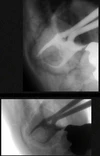

Implant Treatment